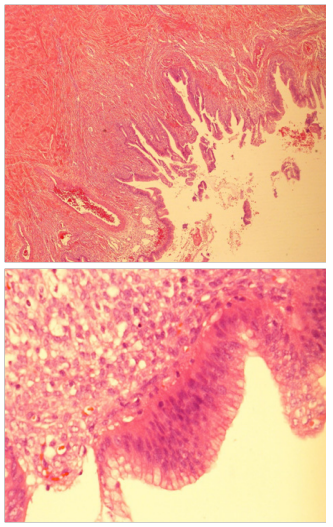

BA, a 12 years old girl was admitted through the ER, for inability to lie flat on the bed for approximately two weeks associated with some reduction in appetite in the preceding month. She had no bowel or urinary symptoms; and her LMP was on the day of presentation; with menarche 11months earlier. She denied any history of jaundice or bleeding disorder in the past. She weighed 39.7 KG, which was in the 3rd centile for her age. On examination she was not anemic and had no significant peripheral lymphadenopathy. Her abdomen was massively distended and one could not discern any organomegaly. The abdomen appeared fluid filled and was dull on percussion with minimal dilated veins on the abdominal wall. Investigations showed normal white cell count and ESR. The Serum AFP, Beta HCG, LDH and Liver function tests and renal function tests were normal. As the mass was not highly suspected to be ovarian in origin, a Ca 125 level or CEA level were not done at this stage. Next an US scan was done. This showed a giant fluid filled mass filling almost the entire abdomen, measuring over 38cms in the longitudinal axis and over 24cms in the transverse axis. The “cyst” was extending from pelvis to xiphi-sternum, compressing bowel loops and liver, moreover, appeared to show either loculation or septa. A clear “cyst” was not identified and the fluid filled mass was inseparably juxtaposed against the lower abdominal wall. The urinary bladder was seen partially filled. As an MRI scan was not immediately available, a CT scan with contrast was done (Figure 1 & 2).

Figure 1 CT scan image AP view showing the giant “cyst” with no clear walls and incomplete septation.

Figure 2 CT scan lateral view showing elevated liver and diaphragm.

This showed a giant fluid filled mass, non-enhancing and without any calcification. The mass had faint septa; but did not show multi-loculation. The mass was compressing the liver and the diaphragm upwards and the bowel loops to the left upper quadrant of the abdomen. One could discern a normal ovary on the left side; but none on the right side. The radiologist felt that a fluid filled mass of lymphangiomatous origin was the first of the possibilities; with ovarian pathology as the next. This was in view of multiple septa seen on US scan, and normal biochemistry and normal tumor markers. As the fluid filled mass was causing orthopnea, it was decided to do a percutaneously drainage using a small tube, at the part where the mass was closely adherent to the abdominal wall, in the low right iliac fossa, using a 6F pigtail catheter. The procedure was uneventful and over the next 3 days, about 7800ml fluid drained. The fluid was almost colorless and cytological examination of the fluid done showed NO malignant cells or atypical cells. The weight of the patient reduced by 8.6KG, with complete relief of orthopnea. She was able to have full normal diet and normal bowel actions. An ultrasound scan was repeated and this confirmed that there was no free fluid in the peritoneal cavity. The cyst was still very large, and the computed residual fluid volume in the mass was 664 ml.